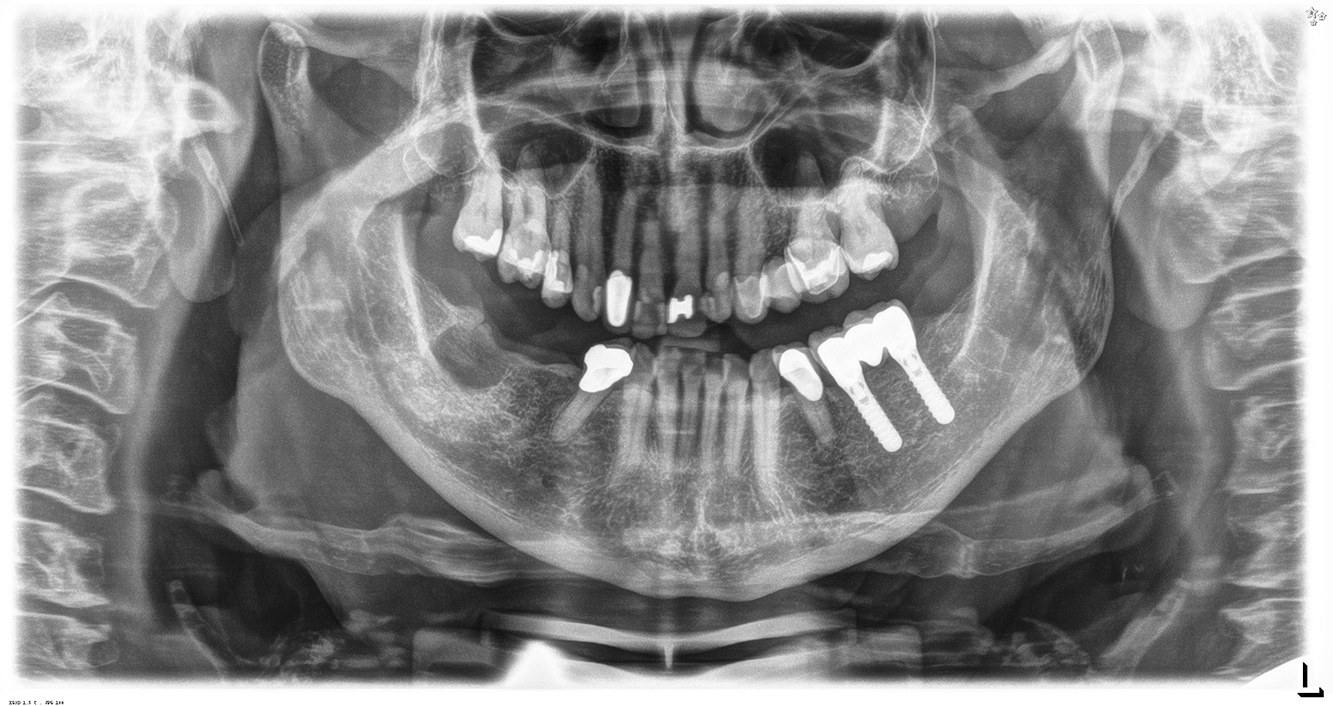

In the medical history, the 55-year-old patient states that he has no systemic disease and is not taking any medication. The patient’s lifestyle is similarly unremarkable. The patient has a few tooth restorations and two implants (2nd and 4th quadrants). On the basis of current findings, gingivitis is identified in an otherwise stable periodontal condition on the reduced periodontium (stage III, grade A). more

The healthy patient with pre-existing periodontal disease & peri-implantitis

Pacientul în vârstă de 68 de ani nu are nicio afecțiune generală și nu ia niciun medicament care ar putea fi relevant pentru sănătatea sa orală, iar stilul său de viață nu prezintă niciun risc special. Pacientul are două implanturi dentare (cadranul 3, de cinci ani) și un caz anterior de boală parodontală (stadiul IV, gradul B) cu pierderea dinților. În prezent, condițiile parodontale sunt stabile. Cu toate acestea, parodontoza crește semnificativ complicațiile biologice ale implanturilor și există riscul de pierdere a implanturilor (21). Se pot determina patru recomandări pentru ședința de profilaxie. mai multe